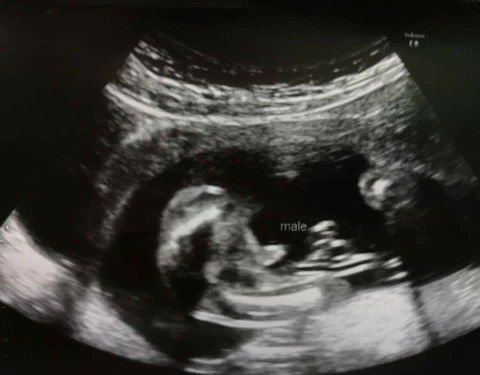

28มกราค่ะ #boy รู้ตอน12w เจาะเลือดหาโครโมโซมค่ะ

15w6dจ้า ไปซาวเสียเงินเองที่คลีนิค ได้ผช จ้า

แม่รู้เพศน้องตอน 15 วีค 1 วันคะ เพชชายคะ

บ้านนี้รู้ตั้งแต่16วีคคะใด้ลูกสาว

เพศชาย ท้องแรกเหมือนกันค่ะ